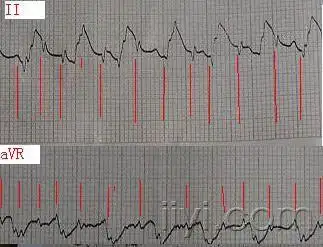

4,心室自身节律(即心电机械分离):心室肌呈慢而微弱的收缩(20~30次

三,心搏骤停的心电图表现 心脏停搏 电机械分离 室颤:qrs-t波群消失

电机械分离

房室分离 - 心电图脑电图专业讨论版 - 爱爱医医学论坛